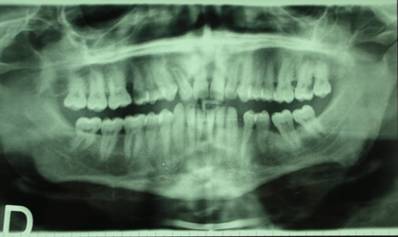

The intraoral examination revealed destructive decay of tooth number 12 and necrotic residues of teeth 15 and 27 (Fig. 1).

Fig 1

RX-OPT of the patient